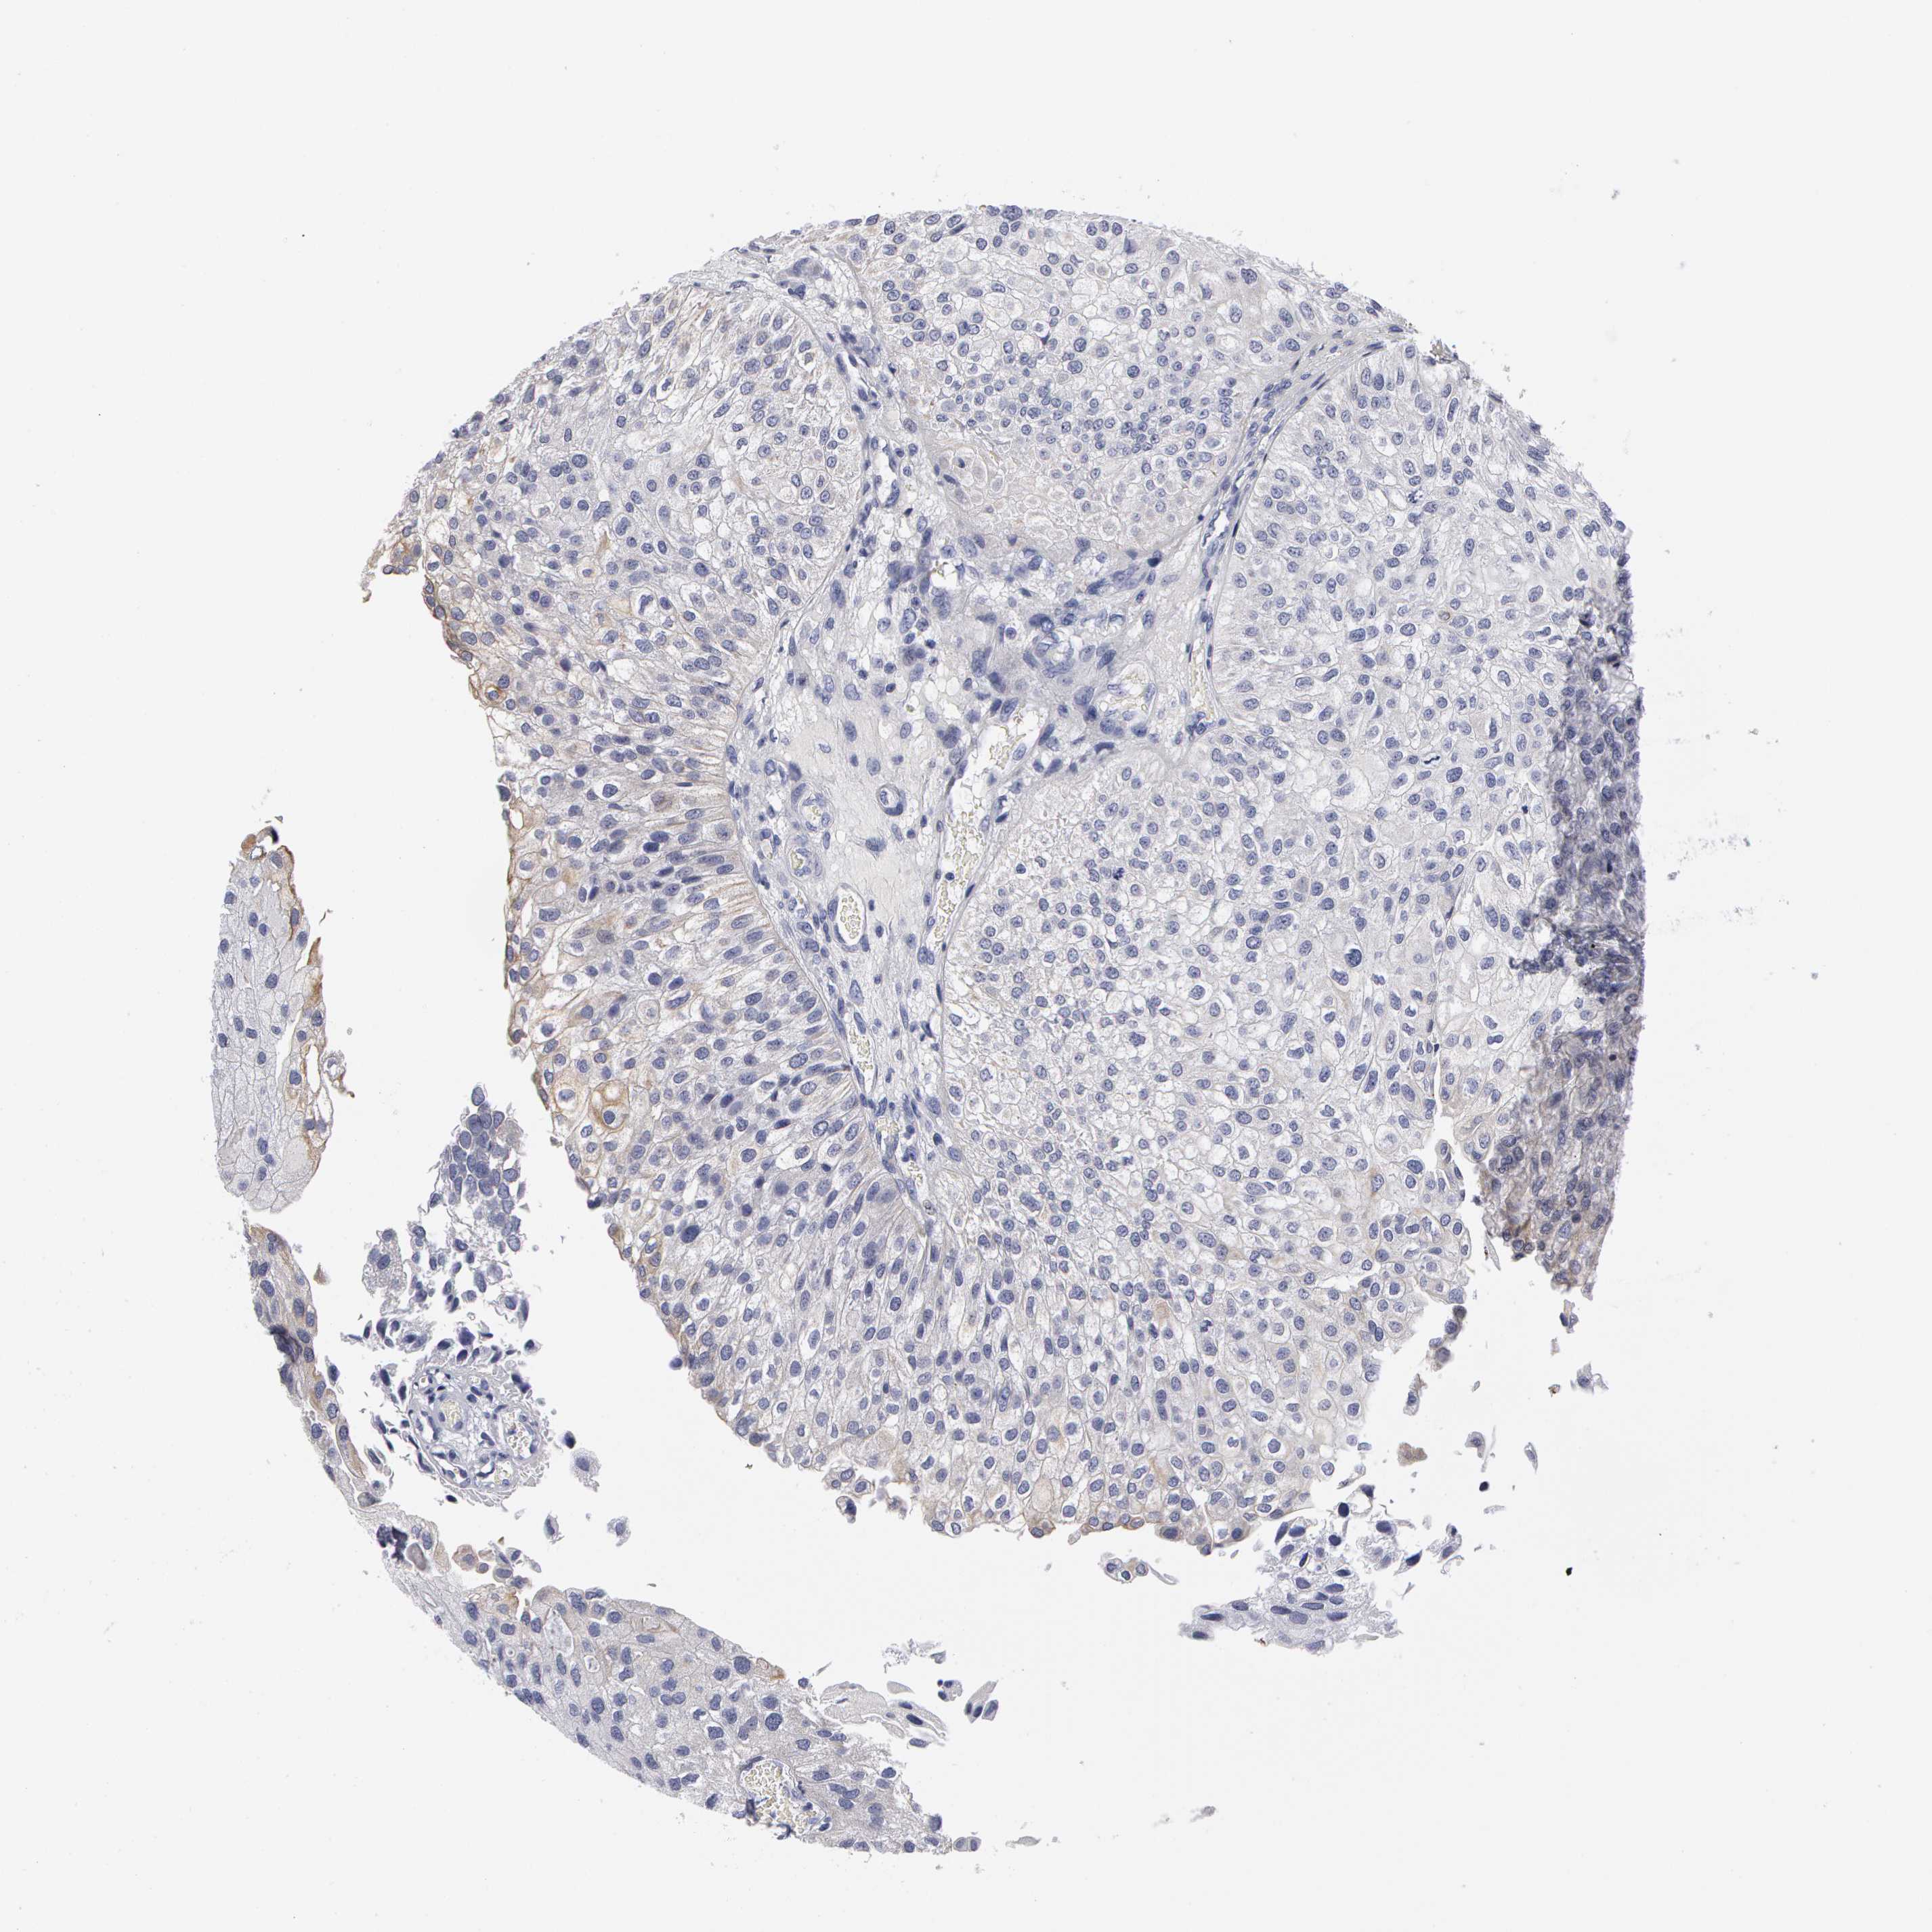

UROTHELIAL CANCER - Protein expressioni

A mouse-over function shows sample information and annotation data. Click on an image to view it in a full screen mode. Samples can be filtered based on level of antibody staining by selecting one or several of the following categories: high, medium, low and not detected. The assay and annotation is described here.

Note that samples used for immunohistochemistry by the Human Protein Atlas do not correspond to samples in the TCGA dataset.

Antibody stainingi

Antibody staining in the annotated cell types in the current human tissue is reported as not detected, low, medium, or high, based on conventional immunohistochemistry profiling in selected tissues. This score is based on the combination of the staining intensity and fraction of stained cells.

Each image is clickable and will lead to virtual microscopy that enables deeper exploration of all samples and also displays staining intensity scores, fraction scores and subcellular localization as well as patient and tissue information for each sample.

Antibody HPA001500

Staining

High

Medium

Low

Not detected

Intensity

Strong

Moderate

Weak

Negative

Quantity

>75%

75%-25%

<25%

None

Location

Nuclear

Cytoplasmic/membranous

Cytoplasmic/membranous,nuclear

Urothelial carcinoma, High grade

Urothelial carcinoma, Low grade

Adenocarcinoma, NOS